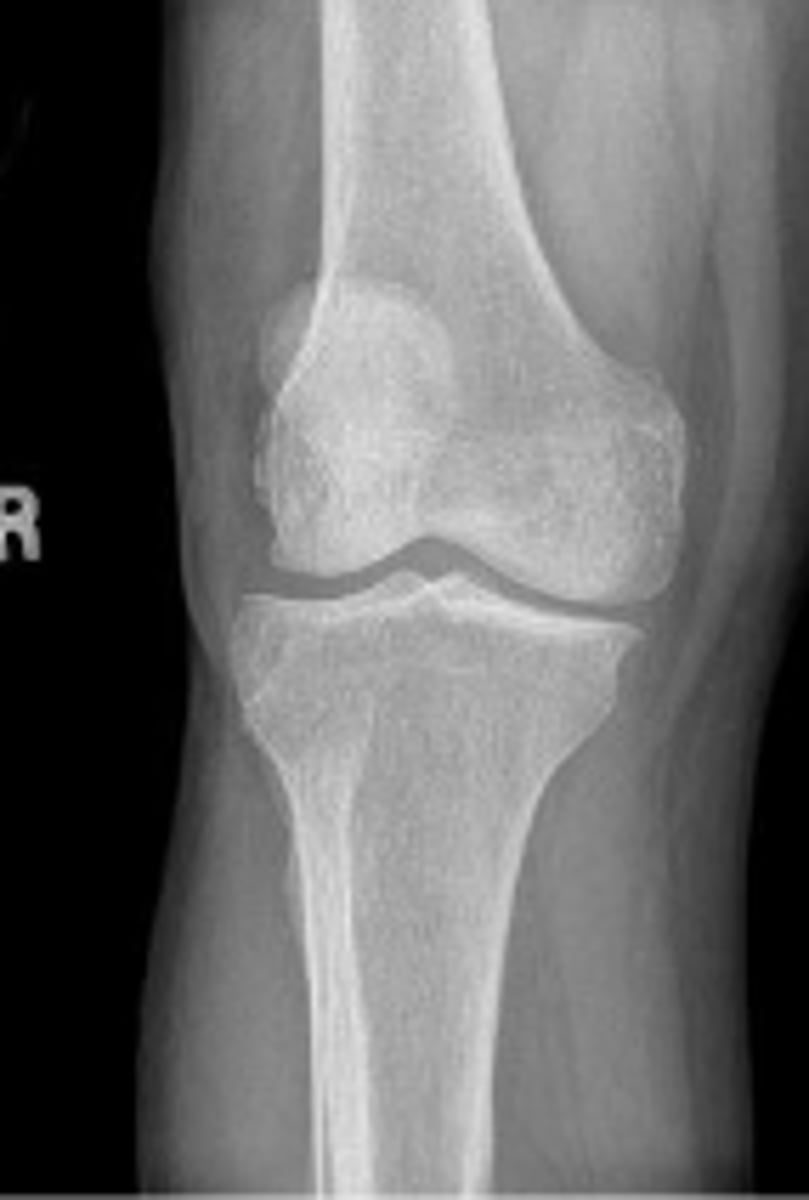

Right internal oblique knee

What is the name of the radiographic view?